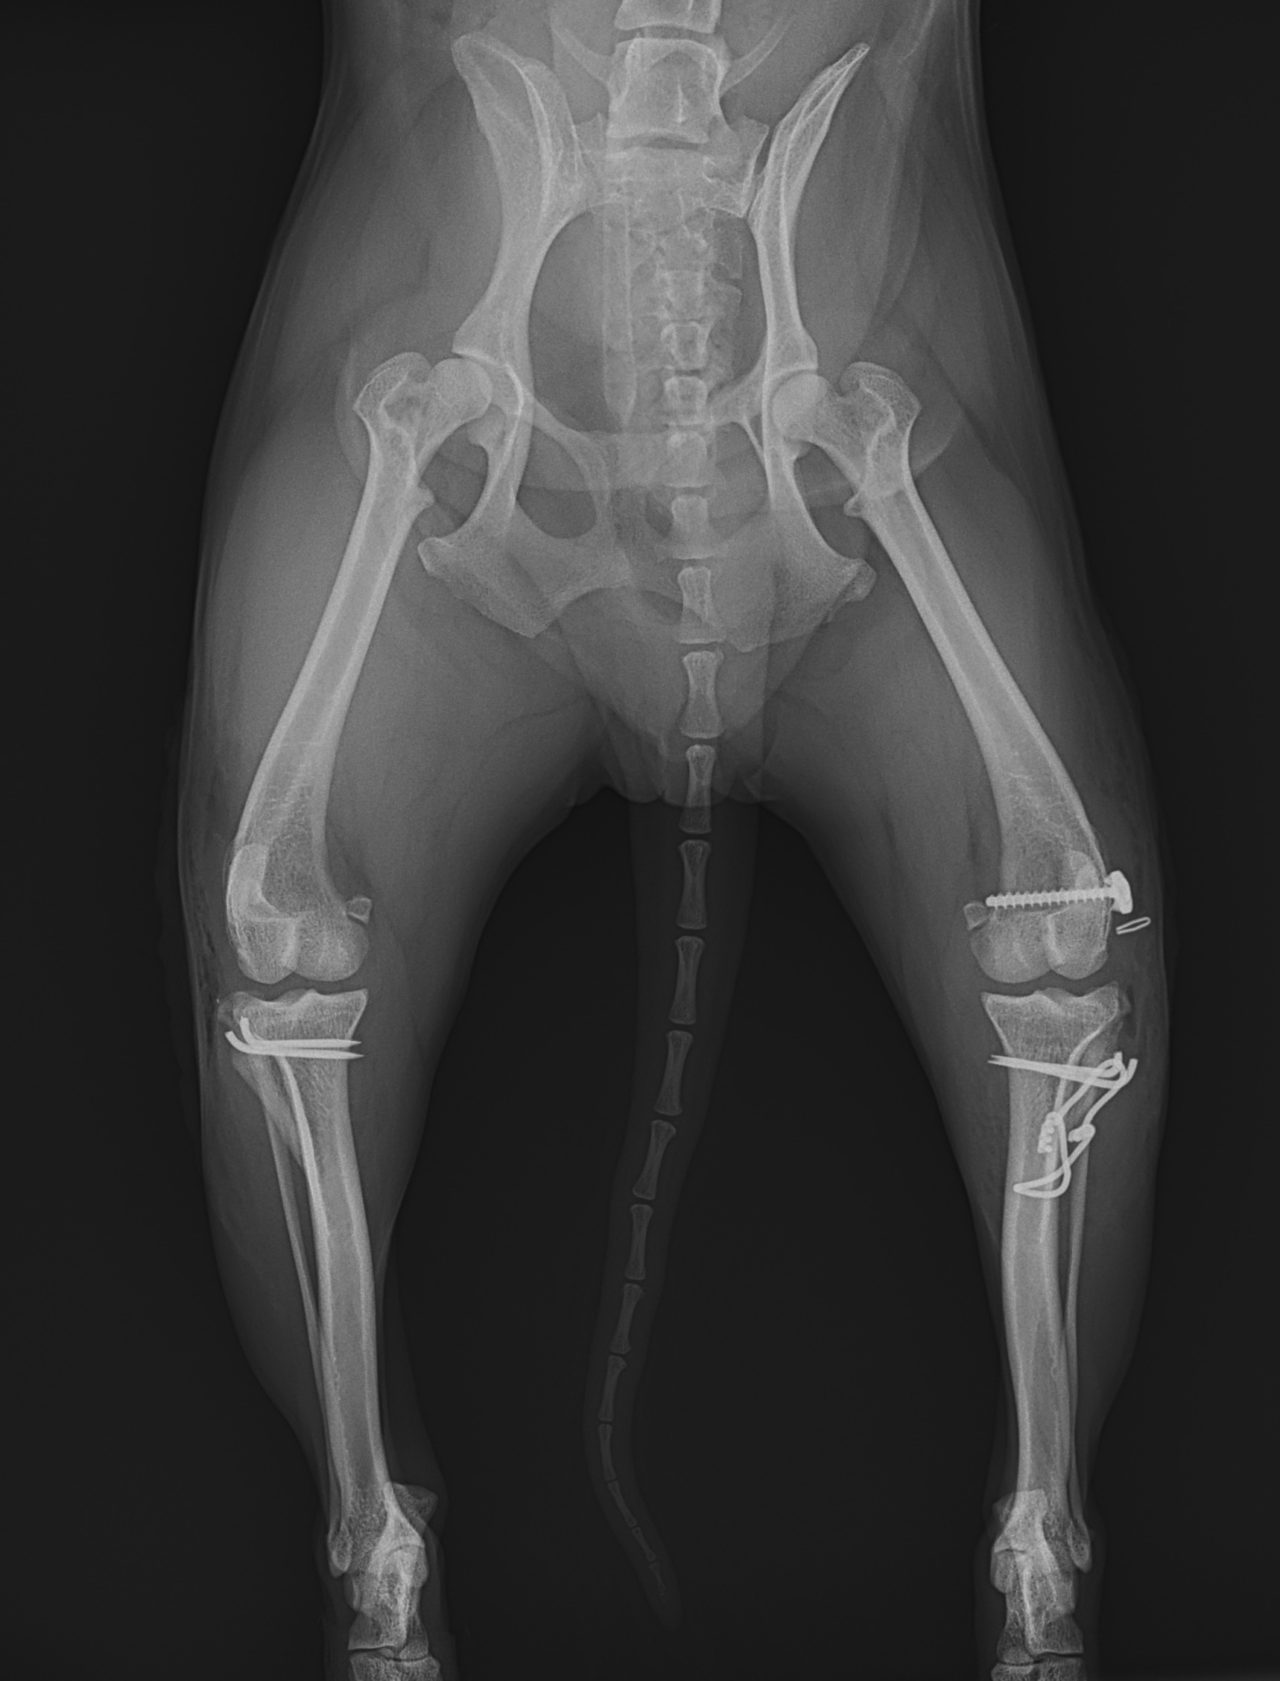

膝蓋骨内方脱臼G3に前十字靭帯断裂併発

5歳のToy Poodleさん。子犬の時から膝蓋骨内方脱臼(パテラ)があったそうですが、今まで特に症状もなく元気に暮らしていました。しかし、ここ1ヶ月で、跛行が目立つよになってきたとのことでかかりつけ医を受診しました。前十字靭帯断裂を併発してしまったようです。ドロアーサイン、ファットパッドサイン、脛骨圧迫試験が陽性でした。そのため、膝蓋骨内方脱臼を整復すると同時に、大腿骨遠位にアンカースクリューと脛骨近位にホールを開け人工靭帯法(ラテラルスーチャー)で安定化させました。